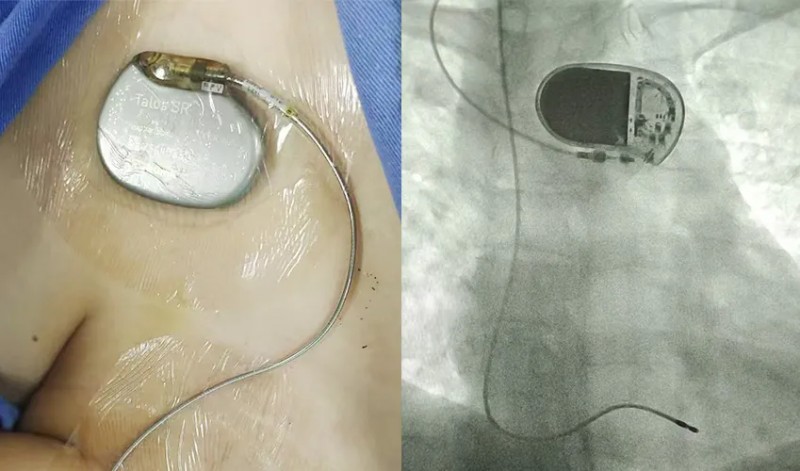

面对上述情况,赵跃武主任医师团队另辟蹊径,立刻经颈静脉途径使用主动起搏电极为患者进行了过渡性起搏器植入。这种方式恰好解决了既往普通临时起搏的两点不足:一是主动电极头端柔软,降低了右心室穿孔风险。二是这种方式可以使用1个月,能够给心脏提供足够的传导恢复时间。

赵跃武指出,确诊三度房室传导阻滞后,最有效的治疗方法就是“永久起搏器植入”。但是,部分三度房室传导阻滞患者仍有可能恢复正常传导。在传导恢复之前,可以使用过渡性起搏器技术。过渡性起搏技术是通过外接起搏器(起搏器暂不植入体内),为心脏提供短期起搏支持(最长1个月),给心脏一个“修复期”,一旦患者的传导阻滞恢复,即可移除。让一部分患者避免了永久起搏器植入,减轻了患者的机体和经济负担。